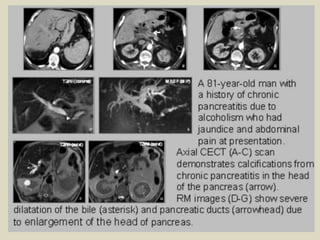

Extrinsic pancreatic disease obstructing the biliary system One of the

more common causes of biliary obstruction is extrinsic disease-benign and malignant.

Pancreatic carcinoma commonly obstructs the distal CBD, and jaundice is often the first

sign of the tumor. As with the primary biliary tract tumors described above, the

characteristic finding at CT, US, or MR is that of abnormal dilatation of the extrahepatic

bile duct to the level of the tumor. Abrupt termination of the bile duct with a short

transition from dilated to nonvisualization is characteristic. Small pancreatic

carcinomas, although not always apparent at imaging, may be critically placed to

cause obstruction. The use of CT and MR contrast techniques that optimize pancreatic

parenchymal enhancement during the late arterial phase can be an aid in visualizing

small tumors. Chronic pancreatitis often creates mass effect surrounding the distal CBD

with biliary obstruction. Calcifications within the head of the pancreas, associated with

chronic pancreatitis, can aid in distinguishing chronic inflammation from pancreatic

adenocarcinoma. Pancreatic carcinoma can occur within chronic pancreatitis, however,

making differentiation difficult. The changes that are caused by chronic pancreatitis on

the biliary tree are usually different from those caused by pancreatic carcinoma.

Rather than the mass causing abrupt termination of the bile duct with a short

transition zone, it is more common for chronic pancreatitis to cause gradual narrowing

of the duct with a longer, tapered transition zone when imaged at CT, ultrasound, or

MR. These are only guidelines, however, because severe cases of pancreatitis can

occasionally cause a focal mass with abrupt termination of the bile duct.